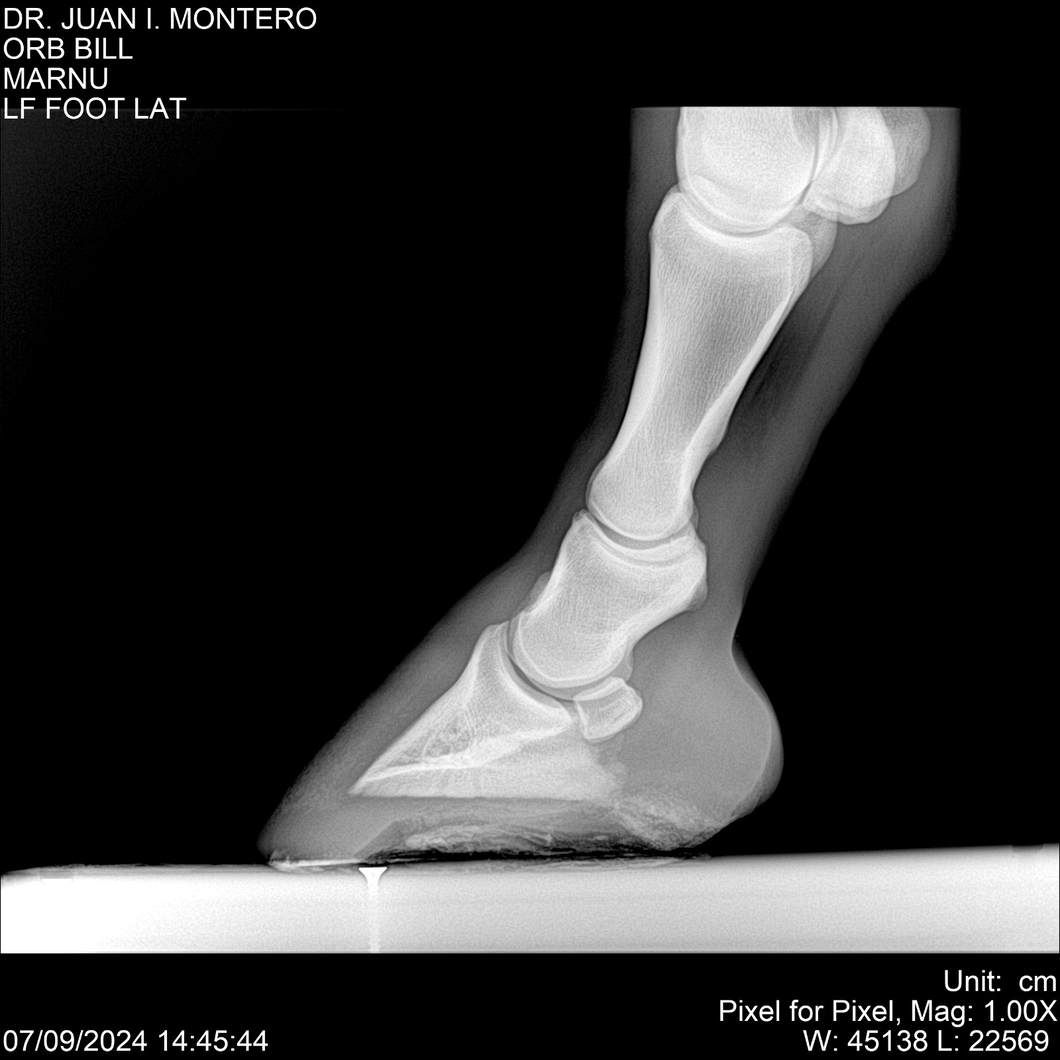

LOTE 7, ORB BILL 🔥 🔥 🔥 Lote Anterior Volver al remate Lote Siguiente Ficha Contacto Montevideo - Ficha del Lote Identificador: #282523 Categoría: Yeguarizos Montevideo - 83 Visualizaciones ClicData Contacto Empresa: Abelenda N. R., Walter Hugo Nombre*: Teléfono* : E-mail* : Mensaje Enviar Registrese gratis Este contenido Exclusivo está disponible sólo para usuarios registrados Ingresar